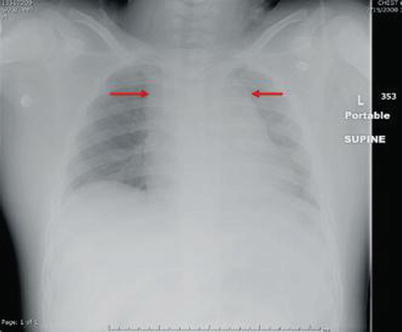

Fig. 15.1

Image of a left flail chest (red ellipse) with associated subcutaneous emphysema (red arrow)

Soft tissue emphysema is another common abnormality that is often identified on radiographic imaging (Figs. 15.1 and 15.2). The presence of soft tissue gas should alert you to look for additional intrathoracic pathology. The most common scenario is subcutaneous air with ipsilateral rib fractures. This constellation of findings should be presumed to signify a pneumothorax, even if not readily identifiable on the radiograph.